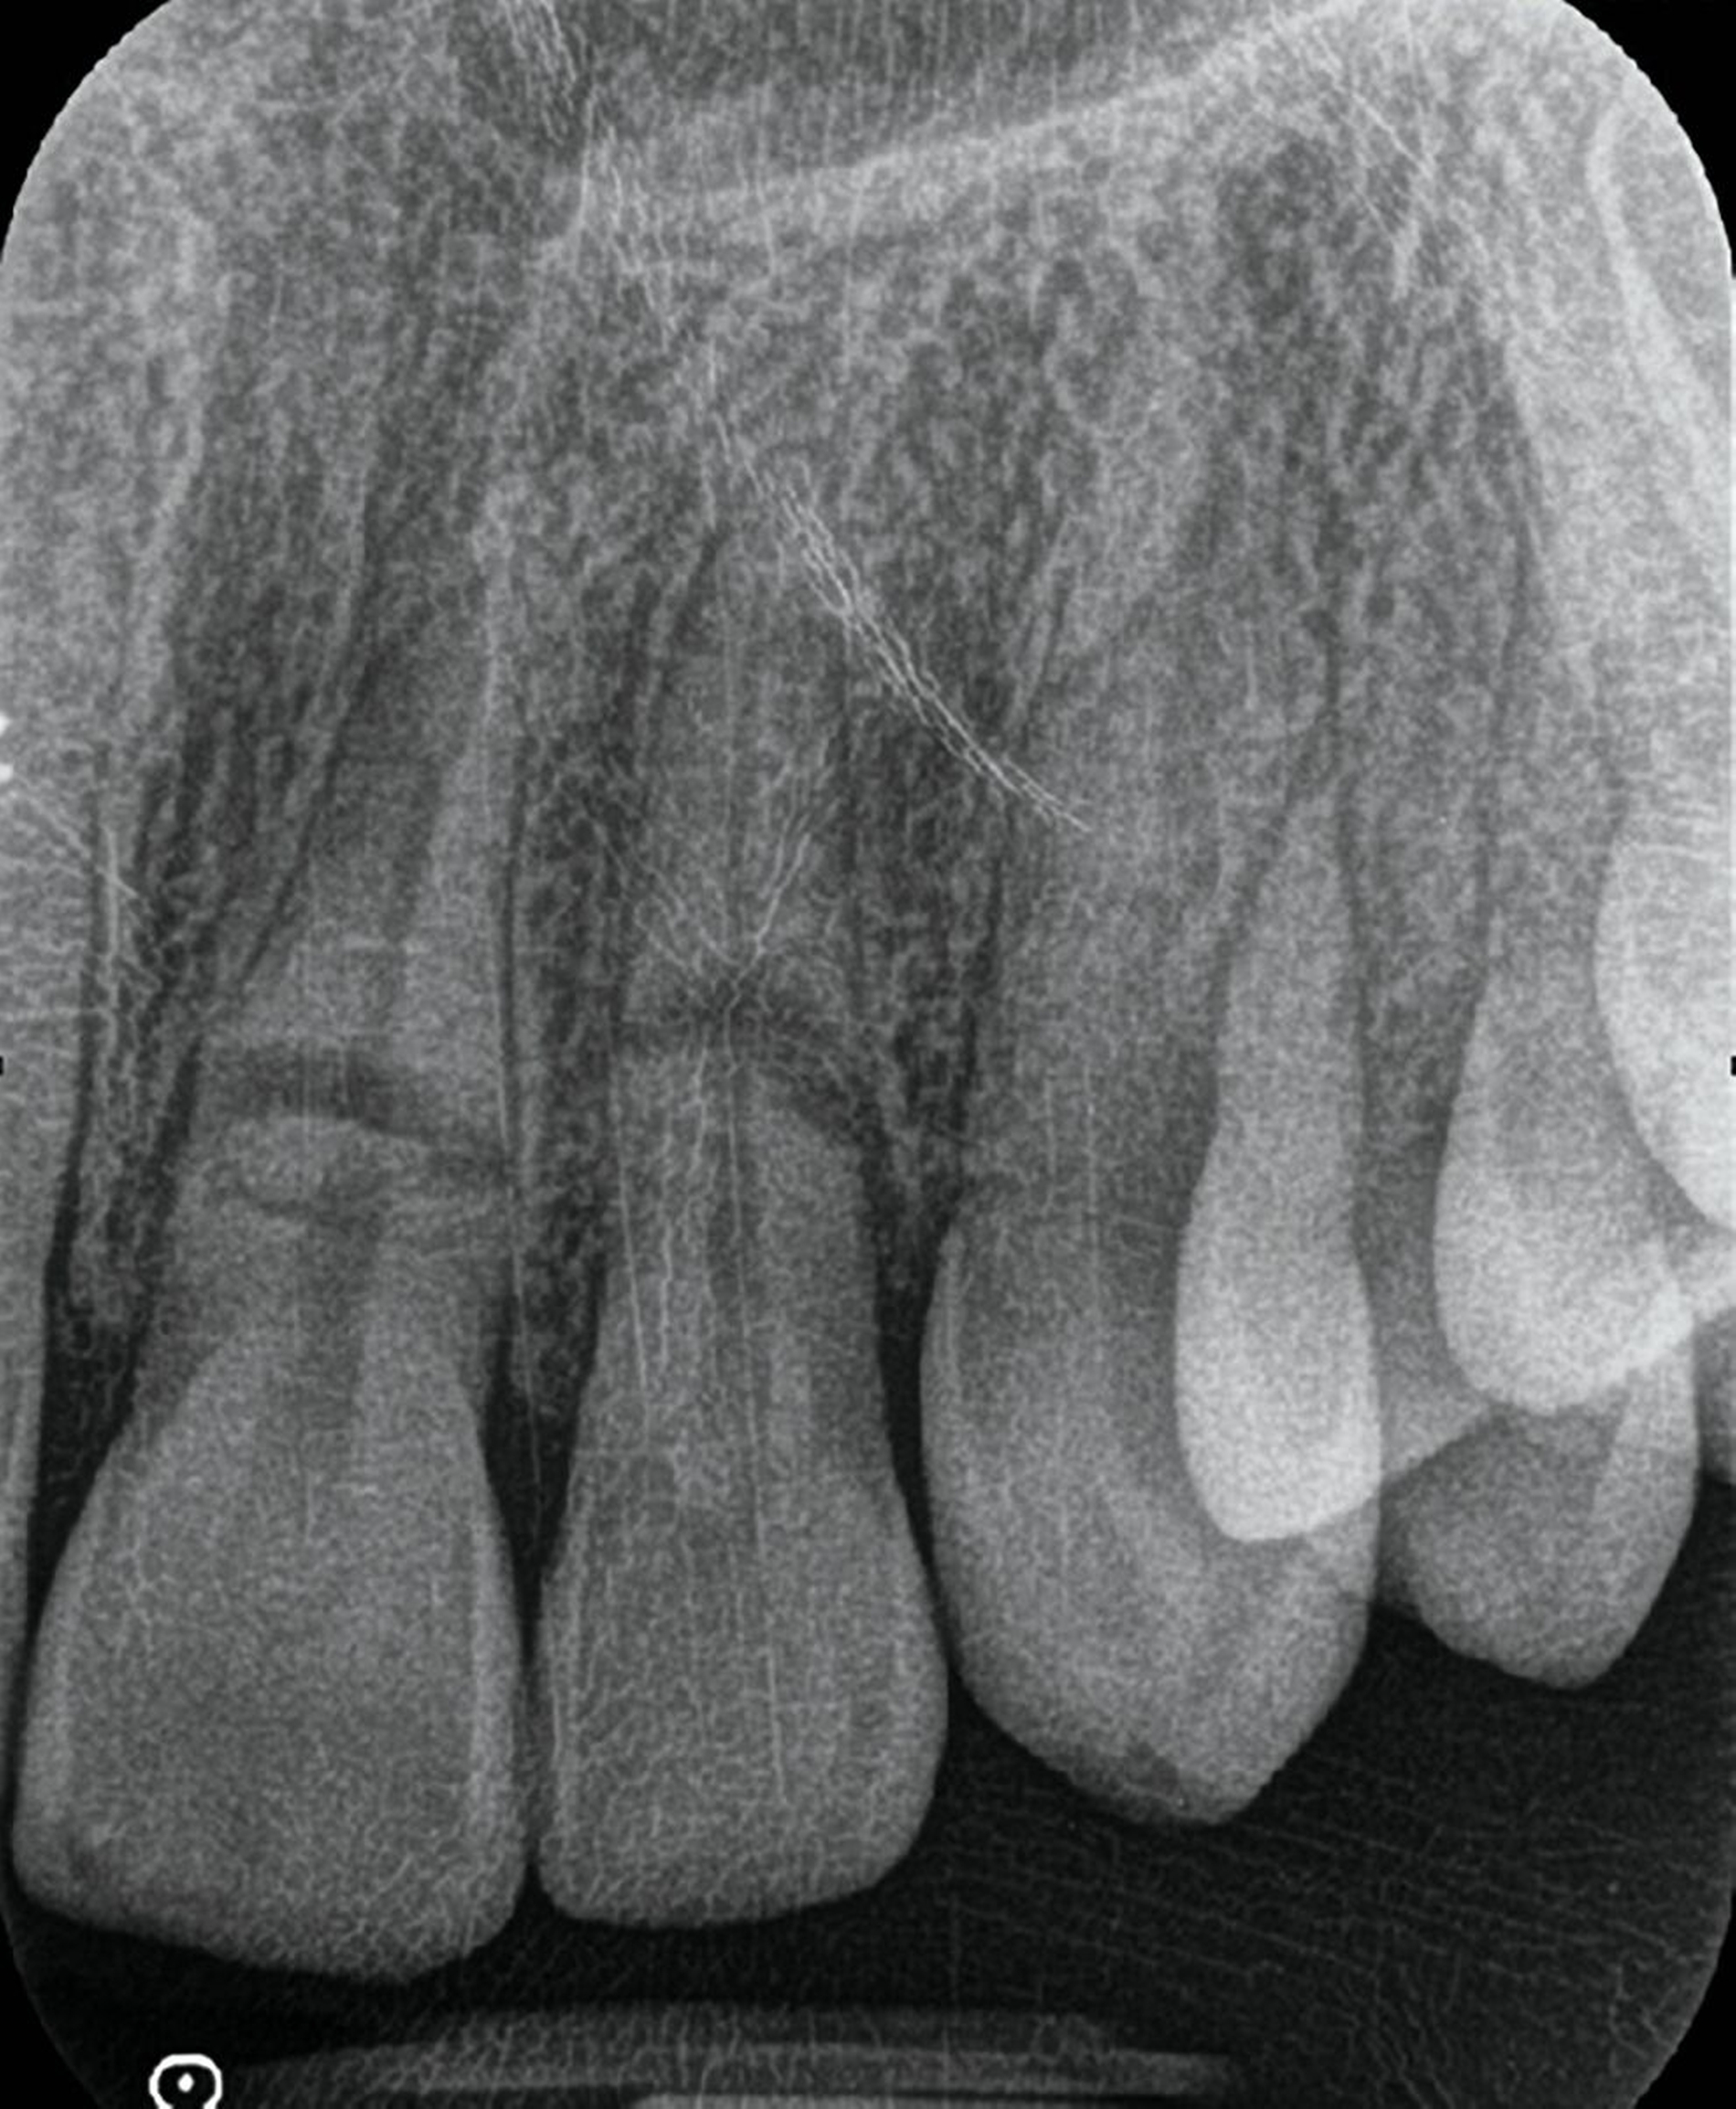

In den meisten Fällen ist die intraorale Zahnfilmaufnahme das diagnostische Mittel der ersten Wahl, da sie eine ausgezeichnete Darstellung von Verletzungen der Zahnkrone, Zahnwurzel sowie begleitenden Knochen- und Parodontalstrukturen bei hoher Auflösung ermöglicht (Abbildung 3). Bei Gefahr der Aspiration von Zahnteilen, etwa durch das Einbringen des Zahnfilmhalters, stellt in praxi die Durchführung eines OPGs als Übersichtsaufnahme eine gute Alternative dar, die den traumatisierten Patienten weniger belastet und zusätzlich einen guten Überblick über die Dislokation von Zähnen oder Zahnfragmenten erlaubt.

Intraorale Aufnahme (Einzelzahnaufnahme, Zahnfilm)

Zahn-/Wurzelfrakturen

Dislokation von Zähnen oder Zahnfragmenten

Integrität der Knochen- und Parodontalstrukturen (zum Beispiel Veränderung von Form und Verlauf des Parodontalspalts)

Stadium der Wurzelentwicklung, Größe des Pulpenkavums

Externe und interne Resorptionen, apikale Aufhellungen (apikale Parodontitis, laterale Parodontitis)